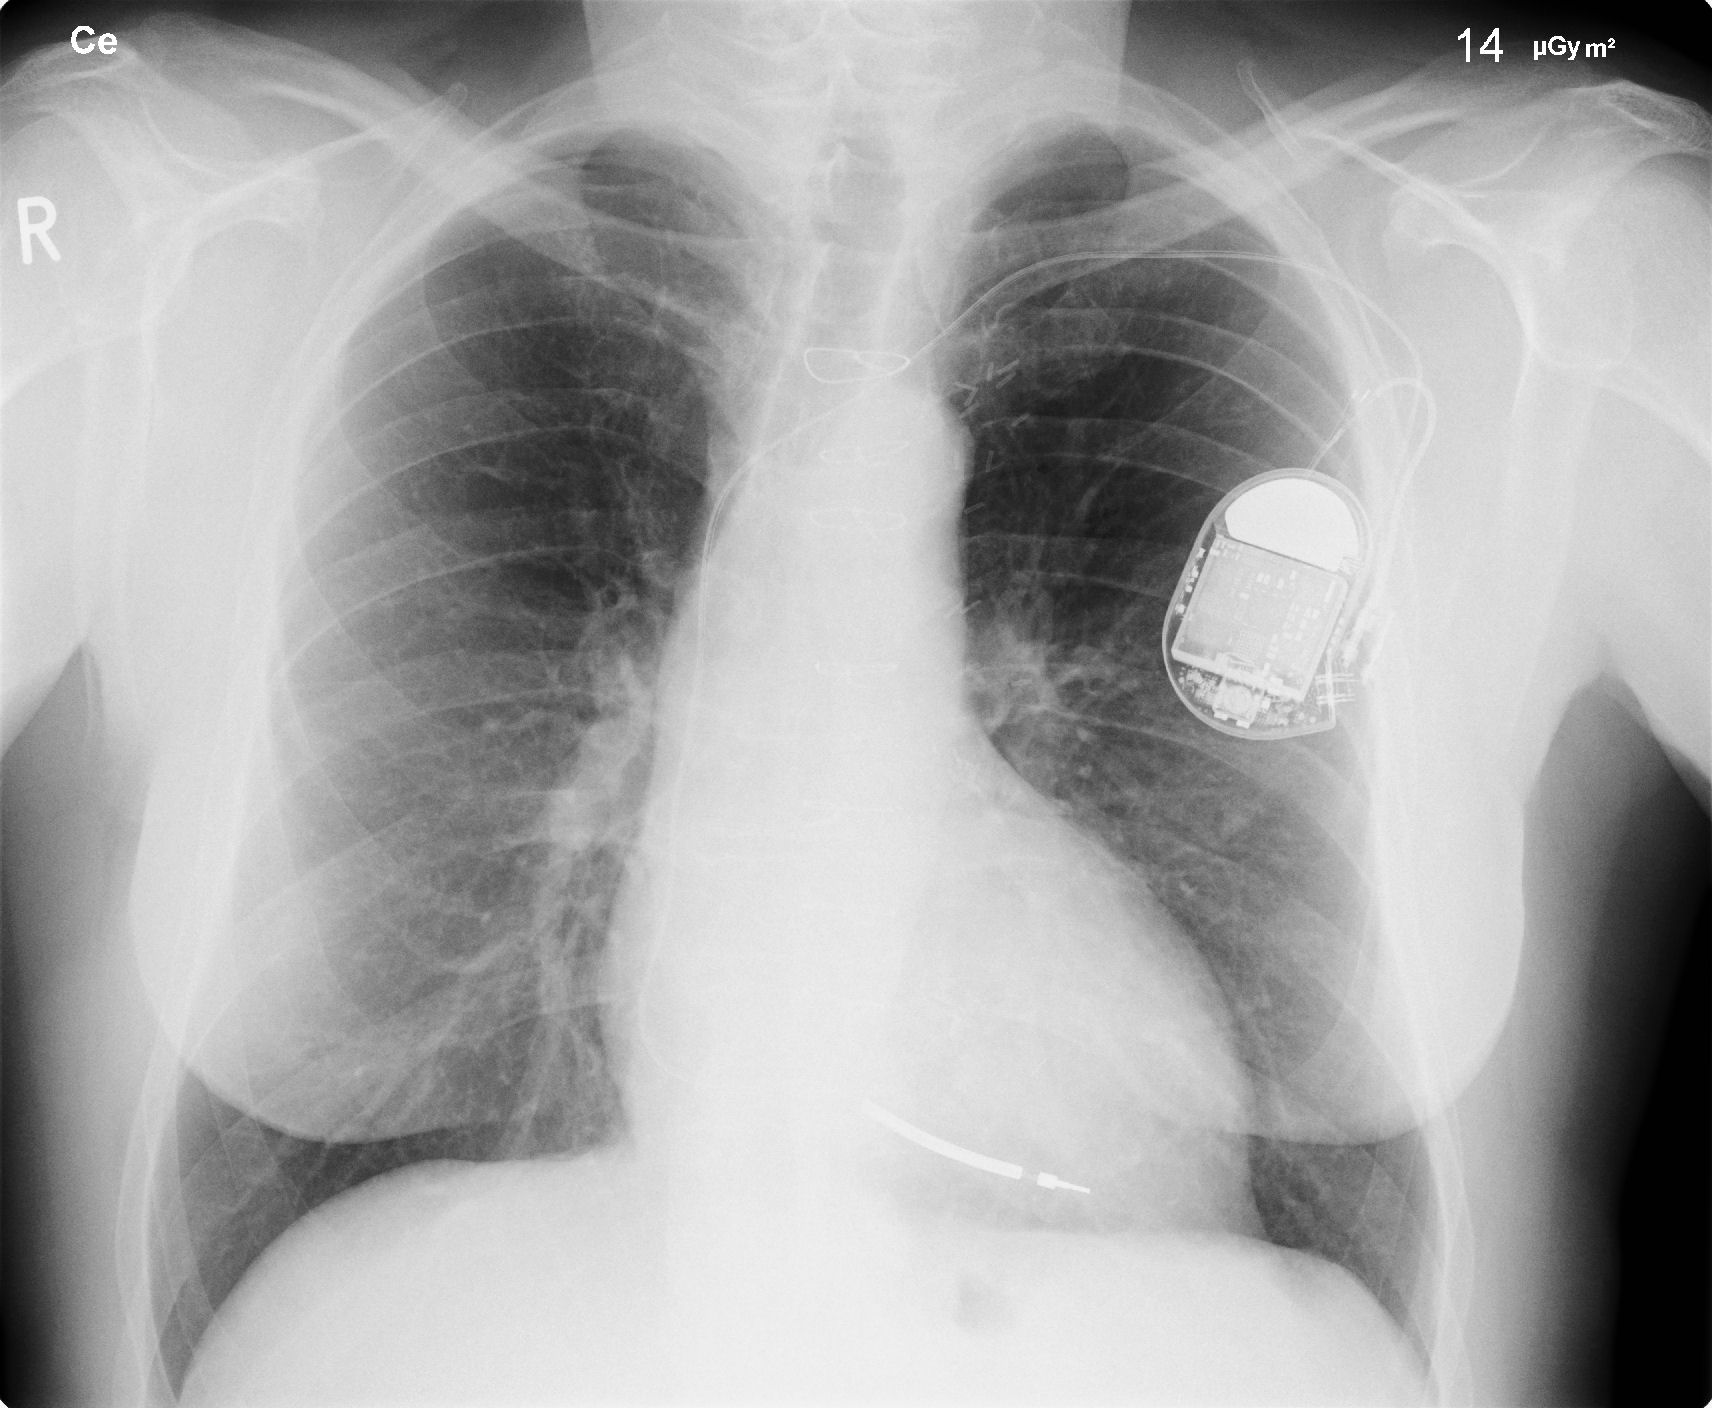

As another sign that the world is becoming interconnected on a terrifying level, nearly 500,000 pacemakers were recalled by the US Food and Drug Administration due to hacking risks. Usually, people perceive hackers as a threat with regards to emails, online banking activities, and identity theft. Now, it would seem that computer wizards can shut down a person’s heart if they wanted to.

The recall is due to fears by the FDA that the roughly 465,000 pacemakers made by the company Abbot are vulnerable to hacking due to lax security in the units, The Guardian reports. Before anyone starts thinking that this would mean hundreds of thousands of people are going to get their chests sliced open and the pacemakers taken out, however, this isn’t exactly a standard recall.

For starters, the recall is only a means of getting the word out and forcing the company to actually issue a firmware update. This update would then come with security patches in order to cover the holes that hackers could exploit.

The good news is that so far, no cases of outside tampering of the pacemakers have been found. This could either mean that hackers have not been able to find the holes, to begin with, or they just chose not to mess with the pacemakers.

Even so, the US Department of Homeland Security is still concerned. As a result, it issued a statement saying that “it is recommended that healthcare providers discuss this update with their patients and carefully consider the potential risk of a cyber security attack along with the risk of performing a firmware update”.

In its own statement, Abbott reaffirms that it is committed to making sure that all security vulnerabilities are addressed, Fortune reports. It’s fortunate that the problem was discovered in time before an incident had occurred that cost lives.